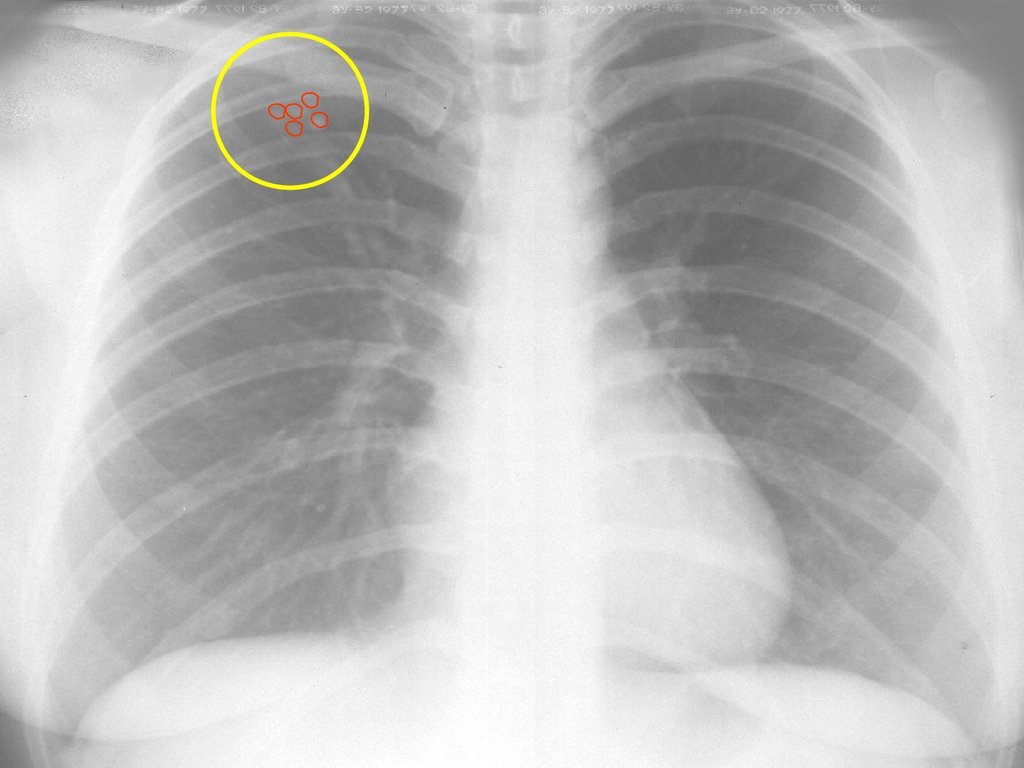

Снимок грудной клетки здорового ребенка: примеры и диагностика

Раздел: Мудрость в объективе